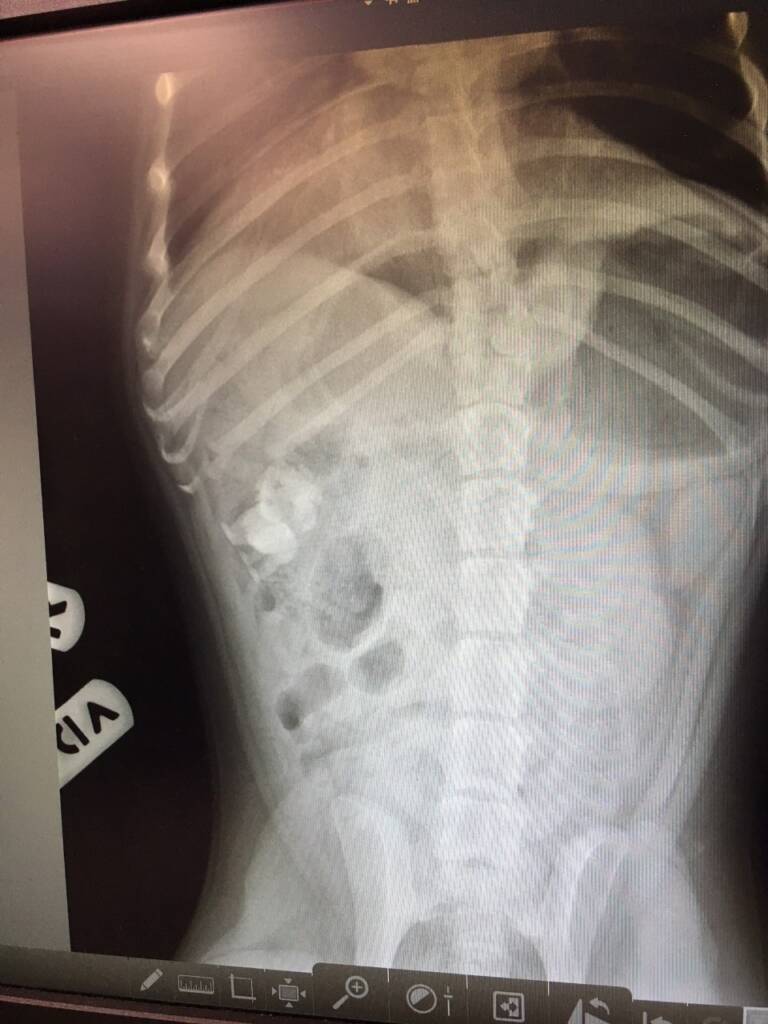

2021 They Ate What?! X-ray Contest winnersThey Ate This: Check out the winner, runners-up, and honorable mentions October 4, 2021 < Previous Entry VOTE NOW! Next Entry > Pages: 1 2 3 4 5 6 7 8 9 10 11 12 13 14